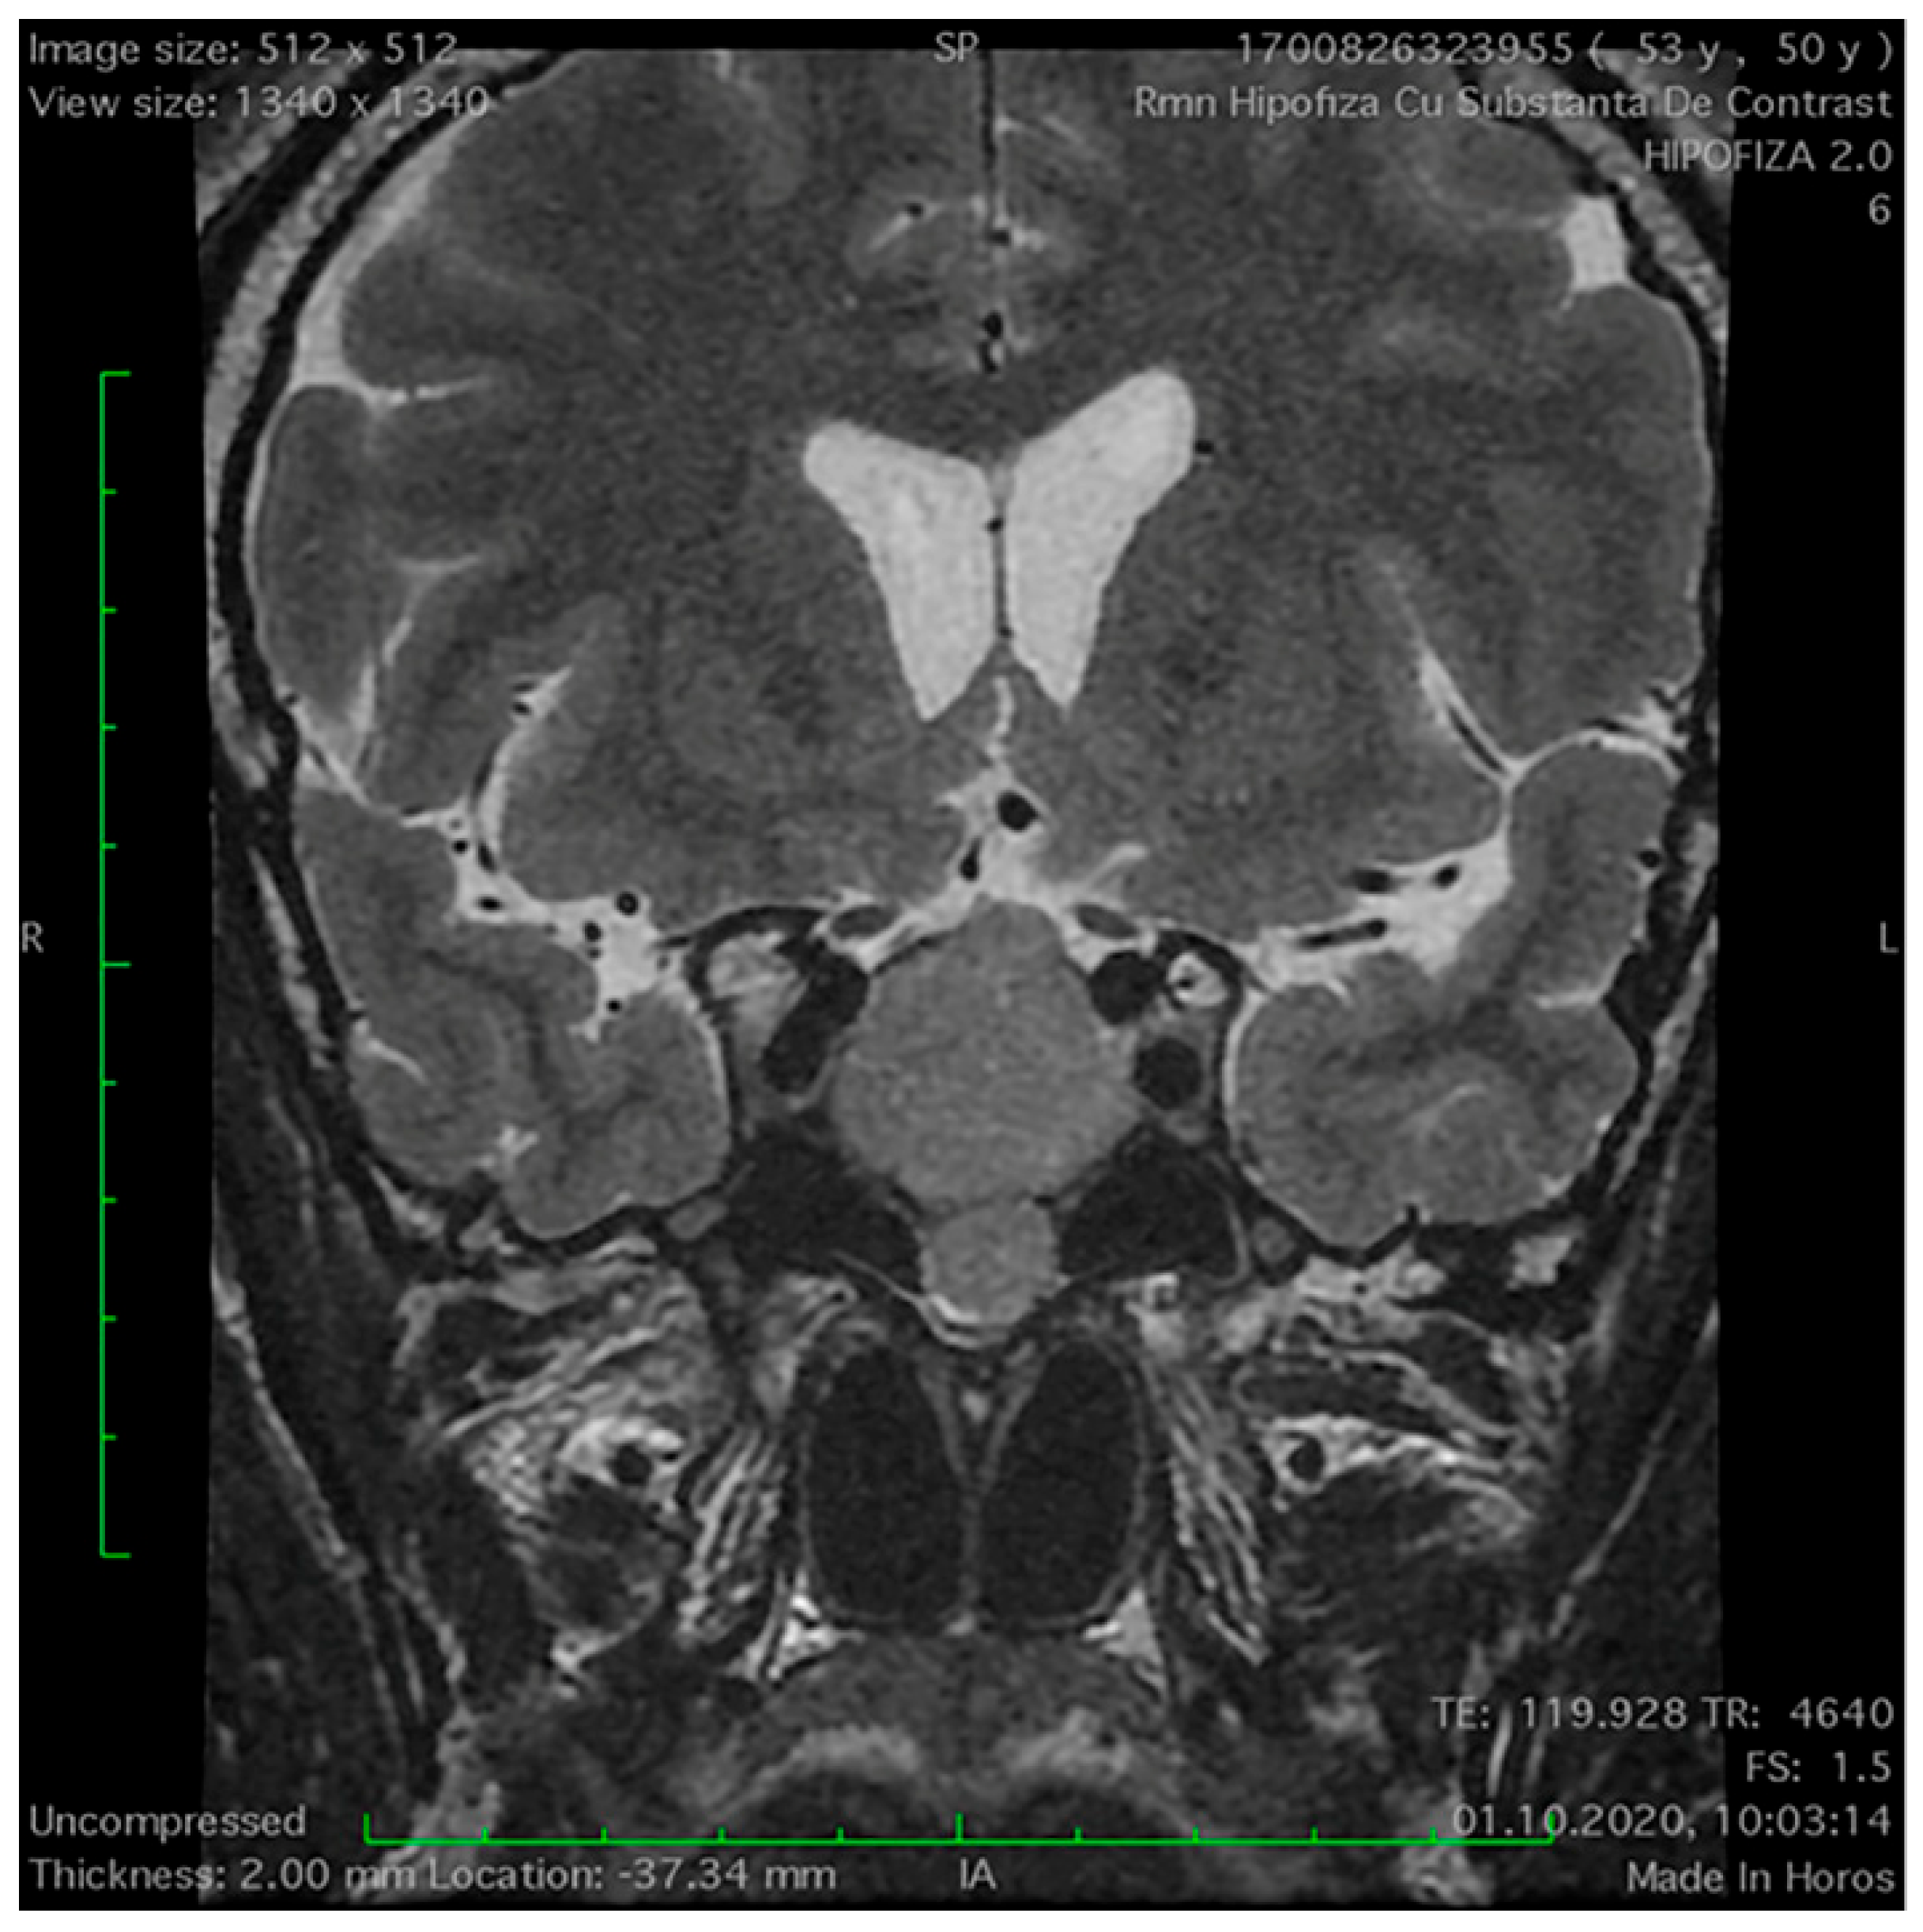

Magnetic Resonance Imaging Features of the Sphenoid Sinus in Patients with Non-Functioning Pituitary Adenoma

2.2. Magnetic Resonance Imaging Study